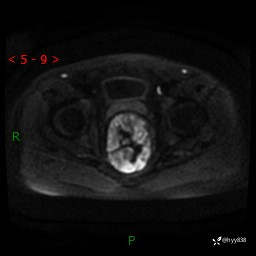

盆腔MRI平扫